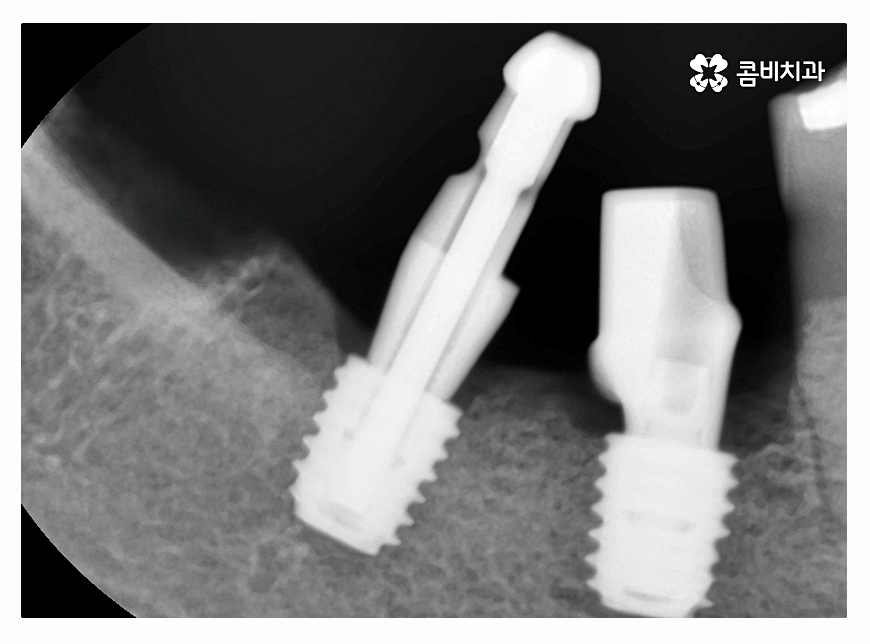

환자분들 개개인의 구강 상태와 치아의 상실 원인 등에

따라서 임플란트종류 및 치료 방법도 달라지게 되지만

임플란트는 자연치아의 심미성과 기능 등을 회복하는 치료이고

첫 치료가 중요하기 때문에 식립 각도와 사후 관리 등도

매우 중요한 부분이라고 할 수 있는데요.

3D CT 등을 활용한 첨단 장비도 중요하겠지만

의료진의 실력과 경험이 무엇보다 중요한 치료라고 할 수 있어요.